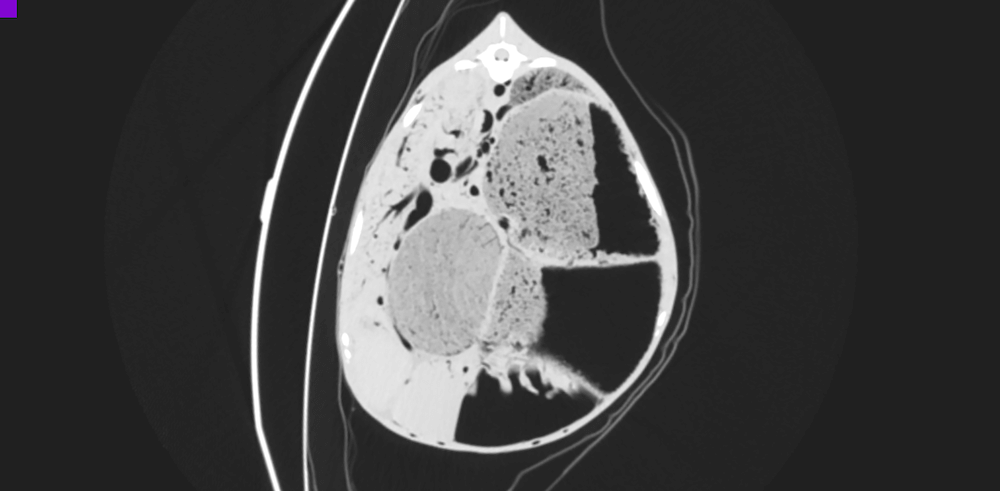

Postmortem imaging in goats using computed tomography with air as a negative contrast agent

Szaluś-Jordanow O., Bonecka J., Pankowski F., Barszcz K., Tarka S., Polguj M., Moroz A., Czopowicz M., Frymus T., Kaba J. 2019.

PLoS One 14(4):e0215758. (IF2017 2,766)